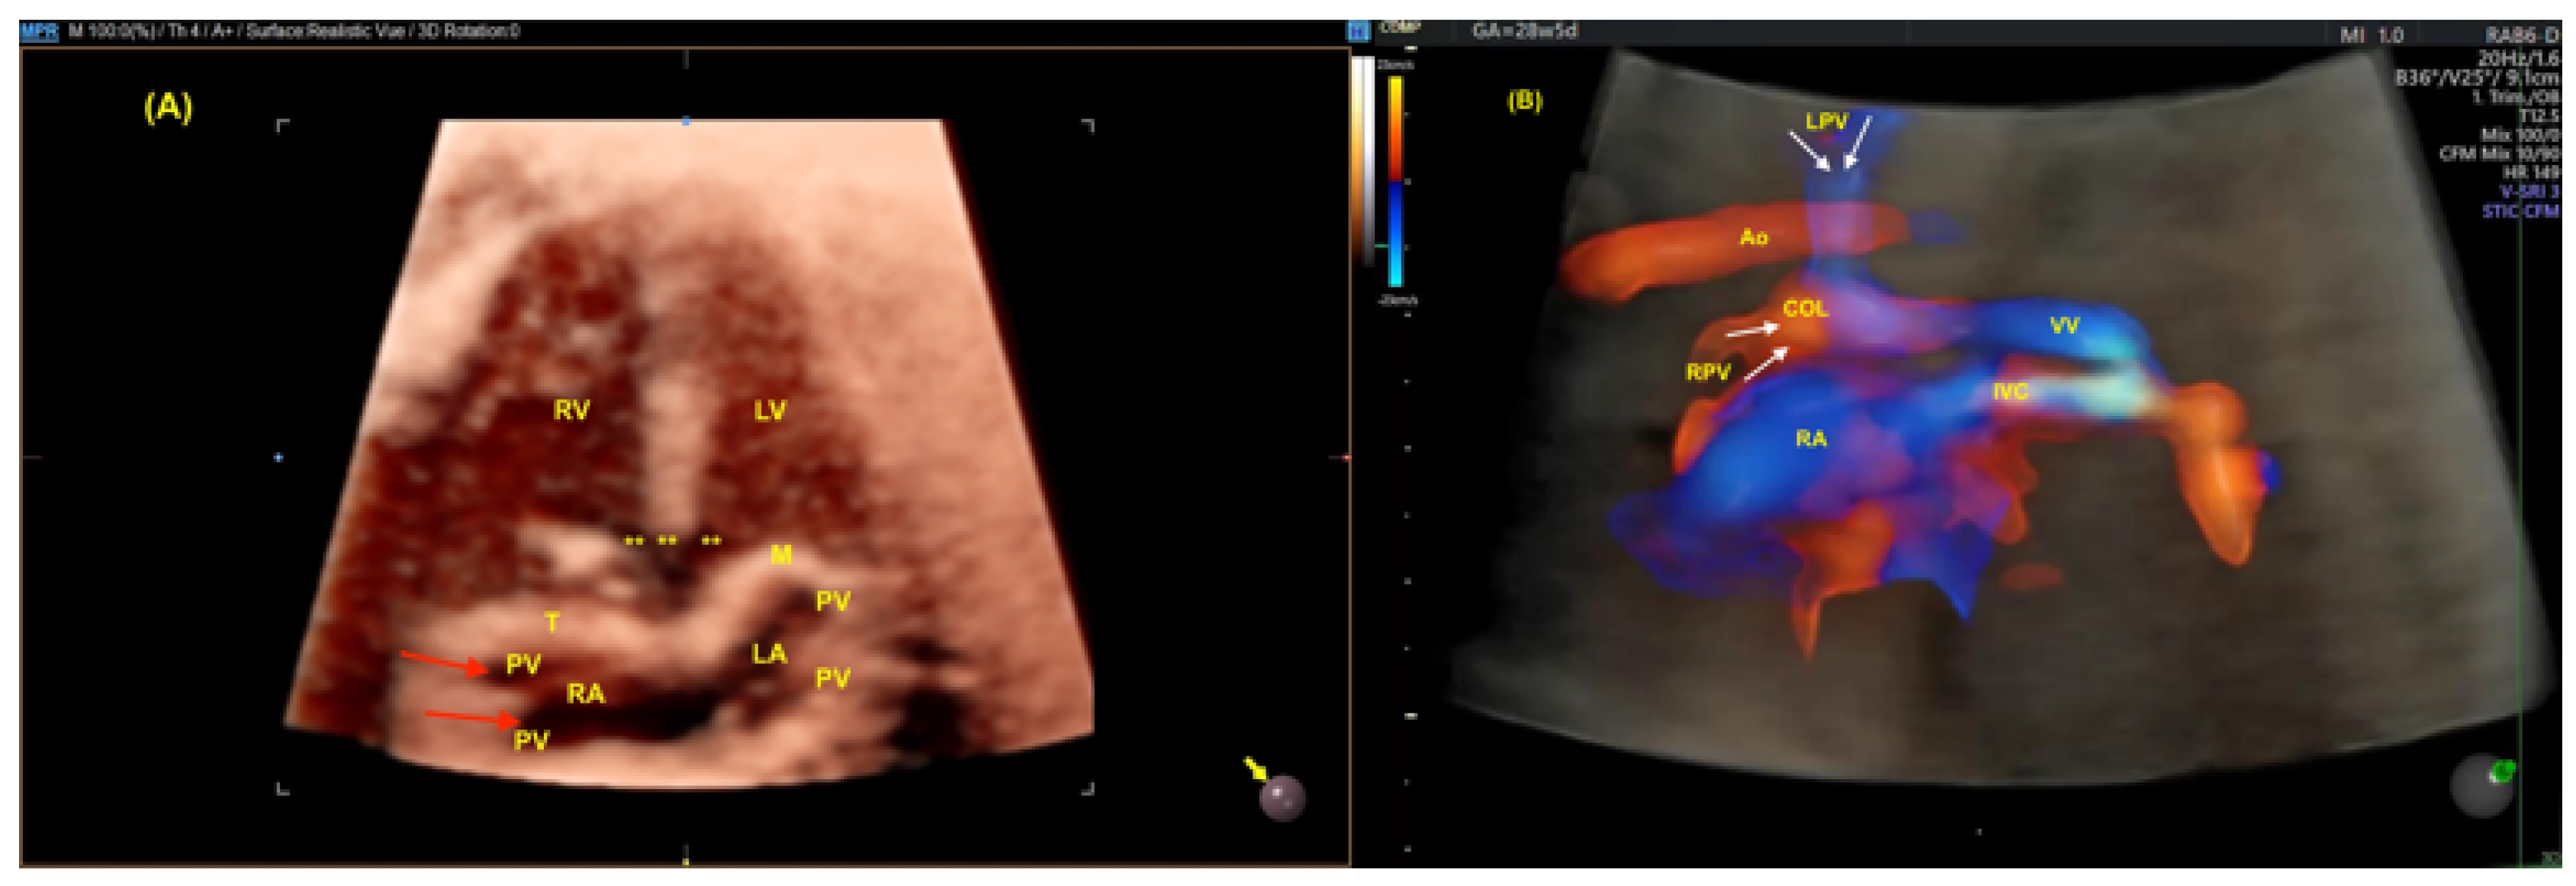

- Malho AS, Bravo-Valenzuela NJ, Ximenes R, Peixoto AB, Araujo Júnior E. Antenatal diagnosis of congenital heart disease by 3D ultrasonography using spatiotemporal image correlation with HDlive Flow and HDlive Flow silhouette rendering modes. Ultrasonography. 2022, 41, 578–596.

- Li TG, Ma B, Gao YH, Zhang RH, Li PL, Da ZQ. Prenatal diagnosis of total anomalous pulmonary venous connection using 2D and HDlive flow combined with spatiotemporal image correlation. Echocardiography. 2022, 39, 1269–1275.

- Bravo-Valenzuela NJM, Peixoto AB, Araujo Júnior E. Prenatal diagnosis of total anomalous pulmonary venous connection: 2D and 3D echocardiographic findings. J Clin Ultrasound. 2021, 49, 240–247.